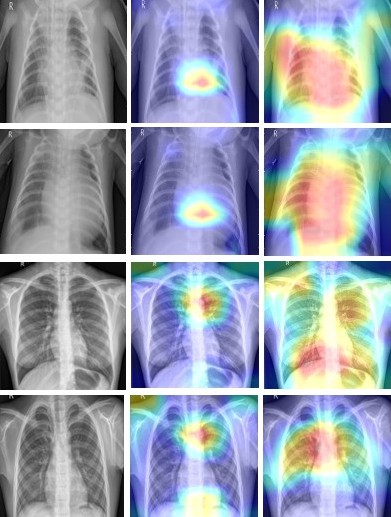

To make the model’s decisions interpretable, Grad-CAM was employed on the entire test dataset for each task. Grad-CAM uses gradient information back-propagated into the last convoluted layer and creates a heatmap indicating the regions of the image that contributed the most to the predicted class. These heatmaps are then overlaid onto the original image, visualizing the model’s attention. The representative examples of these Grad-CAM visualizations for the brain MRI and chest X-ray tasks are illustrated in Figure 6 and Figure 7, respectively. The figures consist of three columns: (1) the original input image, (2) ResNet50 heatmap, and (3) DenseNet121 heatmap. These visualizations illustrate the different attention behavior between the two architectures.

For brain tumor detection (Figure 6), both ResNet50 and DenseNet121 generated localized heatmaps mostly relevant to tumor areas. However, it was observed that DenseNet121 consistently highlighted the core tumor area, which would be very defined, and nearer to the contrast-enhancing or mass-like lesions apparent in MRI. In contrast, ResNet50, while correctly identifying the presence of a tumor, distributed attention on areas that were more diffuse (undefined tumor), and sometimes it developed emphasis on hyper-peripheral areas, and areas that didn’t include the tumor at all, such as the skull or adjacent normal tissue. This suggests that while ResNet50 can capture broad features related to pathology, DenseNet121’s dense connectivity may have focused more sharply on the most discriminative features, avoiding distraction from irrelevant parts of the image.

Refer to caption

Figure 6: Grad-CAM visualizations for Brain MRI: (Left) original MRI image, (Middle) ResNet50 heatmap, (Right) DenseNet121 heatmap. Note how DenseNet121 focuses more precisely on the tumor region, while ResNet50 shows broader, sometimes scattered attention.